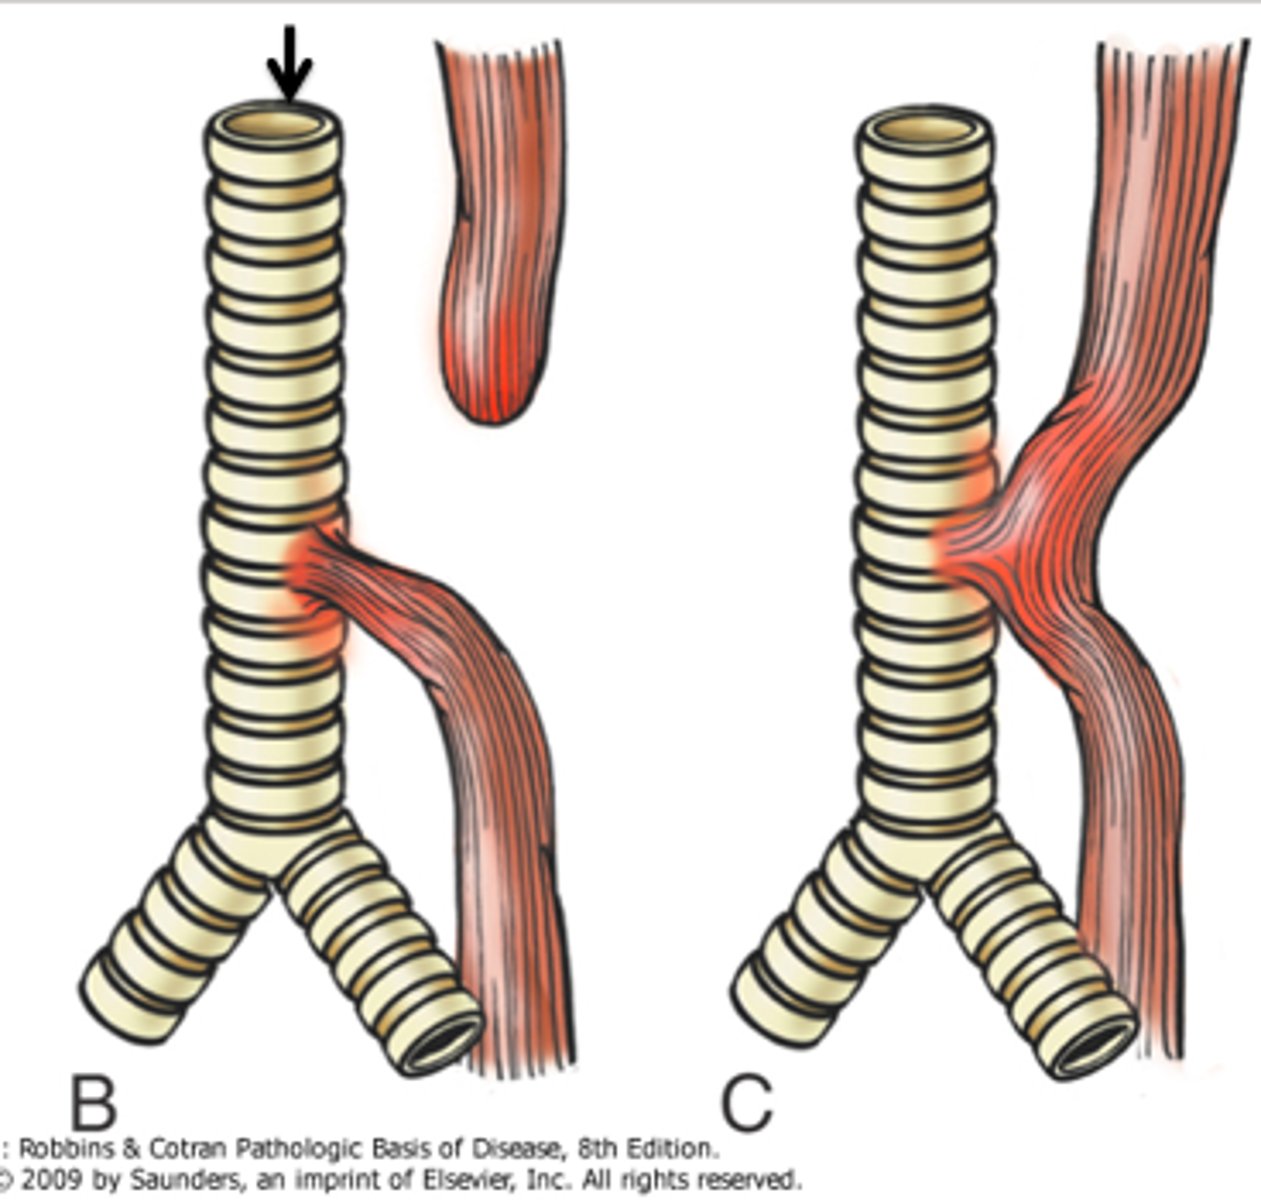

What is the most common congenital esophageal anomaly?

Esophageal atresia

What is the most common tracheoesophageal fistula?

Distal

What is a complication of esophageal atresia?

Absent peristalsis